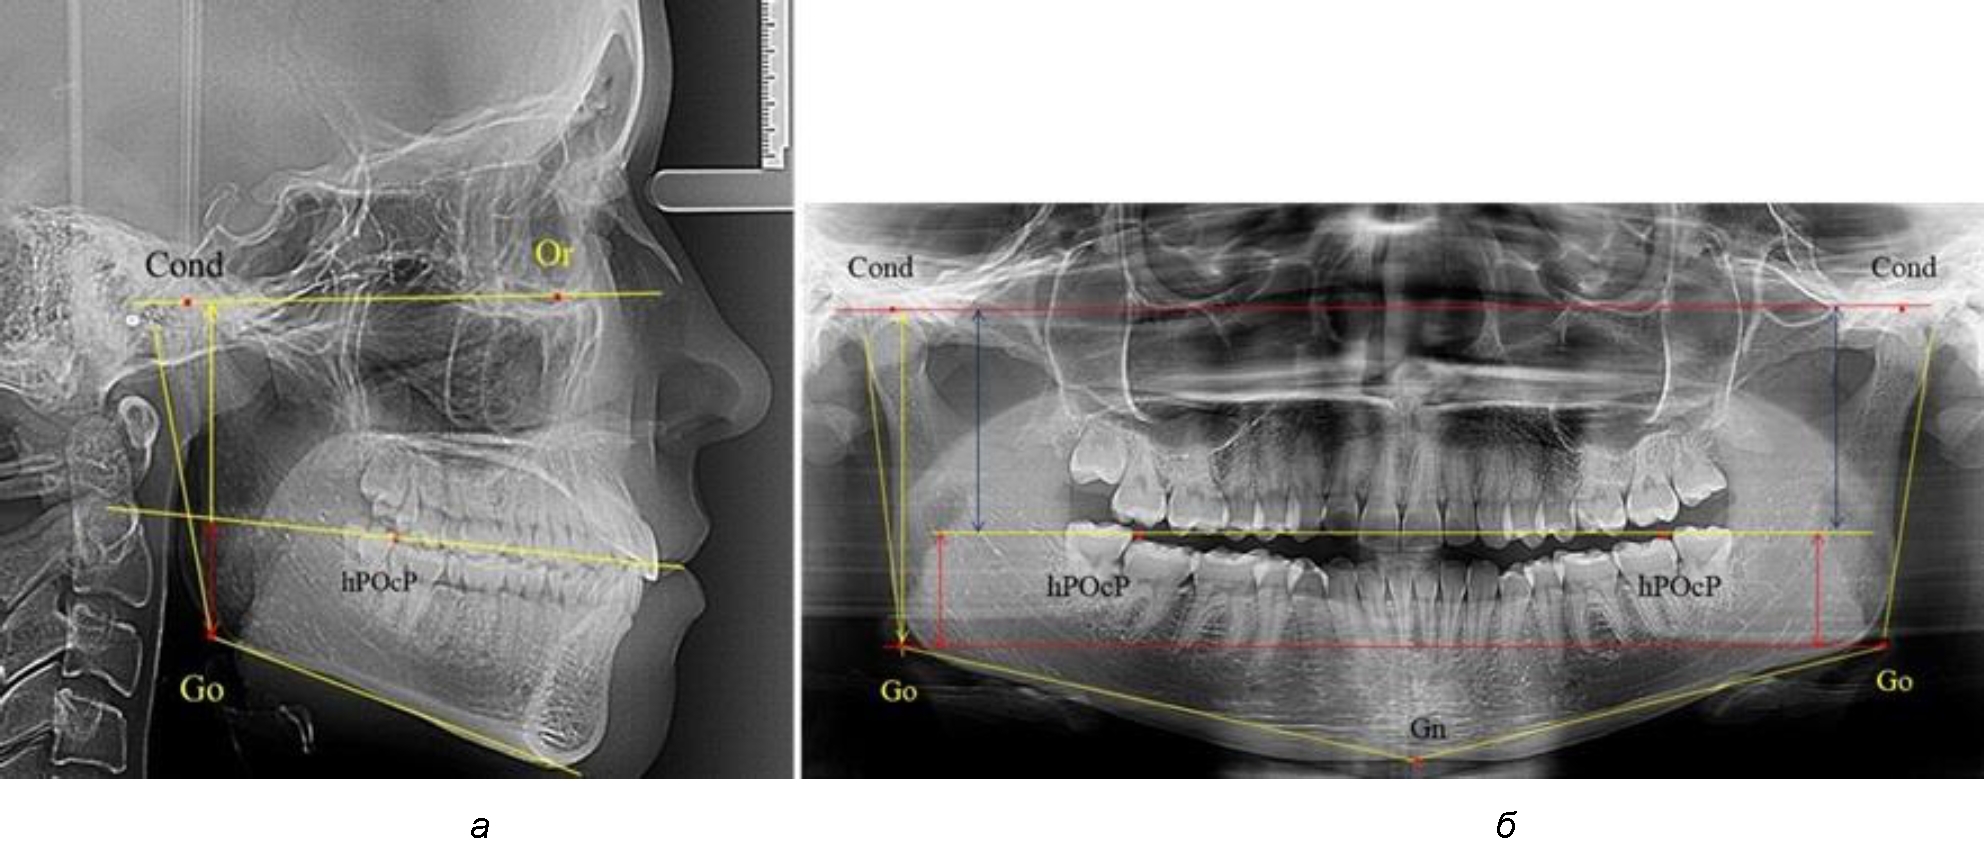

На боковых телерентгенограммах определяли положение верхней точки суставной головки Cond. Касательные линии к ветви и телу нижней челюсти пересекались в точке, которую в клинической практике обозначают как точка угла нижней челюсти или точка гонион Go. Точкой hPOcP обозначали дистальный бугорок нижнего второго моляра вблизи окклюзионного контура коронки, через нее от межрезцовой точки проводили окклюзионную линию, ее продолжали до задней части ветви челюсти. Высоту ветви измеряли как расстояние от угла нижней челюсти до вершины суставной головки Go-Cond. Общую высоту ветви условно делили на 2 части, ее границей служила окклюзионная линия. Верхнюю часть обозначали как окклюзионно-суставная, а нижнюю – как окклюзионно-гониональная.

На ортопантомограмме использовали аналогичные суставные точки Cond на каждой стороне, их соединяли между собой суставной линией Cond-Cond.

Касательная к ветви нижней челюсти соединяла выступающие точку. При построении касательной к телу челюсти проводили в обе стороны линии от точки Gn, расположенной в нижней центральной части подбородочного симфиза, до выступающей нижней точки угла челюсти. Касательные линии при пересечении определяли конструктивную точку гонион Go. Соединение гониональных точек определяло положение гониональной линии Go-Go. При соединении окклюзионных точек hPOcP получали окклюзионную горизонталь (рис. 1). Измеряли расстояние между горизонталями в области ветвей нижней челюсти. Статистический анализ проводили в программе Microsoft Excel. Составляли вариационные ряды с последующим расчетом среднего значения, стандартного отклонения и ошибки среднего ±m. Также оценивали максимальные и минимальные значения величин. Определи относительные величины соотношения верхней и нижней частей ветви нижней челюсти.

Рис. 1. Метод измерения высоты ветви нижней челюсти на телерентгенограмме (а) и ортопантомограмме (б)

3-я подгруппа была с наименьшим количеством анализируемого материала, и здесь было проанализировано 17 комплектов рентгенограмм [(22,97 ± 4,89) %], на которых средняя величина отношения верхней части ветви к нижней составляла 2,45 ± 0,04, что было достоверно больше показателя, полученного по группе в среднем, а также в 1-й и 2-й подгруппе. Визуально параметры ветви отличались от других подгрупп. Высота ветви составляла (57,83 ± 0,89) мм, что было несколько меньше, чем в других подгруппах. Максимальная высота была 64 мм, а минимальная – 53 мм. Высота верхней части составляла (41,03 ± 0,59) мм, что было близким по значениям, полученным в других подгруппах и свидетельствовало о меньшей вариабельности указанного параметра. В то же время высота нижнего отдела ветви была (16,83 ± 0,36) мм и показатель отличался в меньшую сторону, по сравнению с аналогичным размеров в других подгруппах (рис. 4).

Рис. 4. ОПТГ пациента 3-й группы с увеличенным коэффициентом соотношения частей ветви нижней челюсти